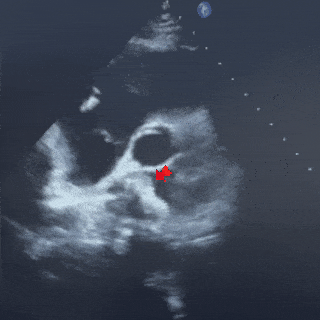

术中超声复测

主动脉短轴切面

缺损12.1mm

合并房间隔膨出瘤

缺损+房间隔膨出瘤23.0mm

四腔心切面

缺损+房间隔膨出瘤24.7mm